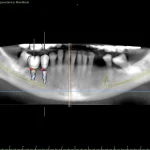

This is the most important advantage. By planning in 3D, the surgeon can "see" through the bone and gum.

- Safety: It allows for the identification and marking of vital anatomical structures (like the inferior alveolar nerve or the maxillary sinus). The surgical guide ensures the implant is placed at a safe distance from these structures, drastically reducing the risk of complications such as paresthesia (numbness of the lip) or sinusitis.

- Precision: It eliminates the guesswork and variability of freehand surgery. The implant is placed with submillimetric accuracy, exactly where it was planned.